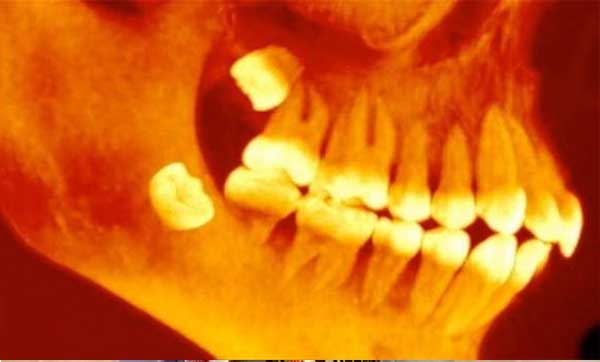

ভারতে সাত বছরের এক শিশু মুখে ৫২৬টি দাঁত নিয়ে ভর্তি হয়েছিলো চেন্নাইয়ের সবিতা ডেন্টাল কলেজ ও হাসপাতালে। এ ঘটনা দেখে তাজ্জব হয়ে যান চিকিৎসকরা। পরে অস্ত্রোপচারের মাধ্যমে তারা ওইসব দাঁত তুলে ফেলেন।

স্থানীয় এক সংবাদ মাধ্যম জানায়, তিন বছর বয়স থেকেই ওই শিশুর ডান চোয়ালের নিচের দিকটা ফোলা ছিলো। কিন্তু বাবা-মা এই সমস্যাকে তেমন গুরুত্ব দেননি। বয়স যত বেড়েছে, চোয়ালের ফোলাভাব আরও বেড়েছে। মঙ্গলবার হঠাৎ করেই শিশুটির মুখে প্রচণ্ড ব্যথা শুরু হয়। এরপর তাকে হাসপাতালে নিয়ে আসেন তার অভিভাবকেরা। তখন নানা ধরনের পরীক্ষা করে চিকিৎসকেরা দেখেন তার মুখে অতিরিক্ত দাঁত রয়েছে, যার কারণে এত ব্যথা হচ্ছে। বুধবার দীর্ঘ পাঁচ ঘন্টা ধরে অপারেশন চালিয়ে সবকটি দাঁত বের করে আনেন চিকিৎসকেরা।

এ সম্পর্কে ওই হাসপাতালের ওরাল ও ম্যাক্সিলোফেসিয়াল সার্জারি বিভাগের চিকিৎসক পি সেনন্থিনাথাল জানান, ‌কমপাউন্ড কসপোসিট অনডন্টোম নামে একটি বিরল রোগে শিশুটি আক্রান্ত। এক্স রে ও সিটিস্ক্যান করার পরেই ডান চোয়ালের নিচের দিকে কতগুলি অপরিণত দাঁত দেখতে পাই। তখনই আমরা অস্ত্রোপচারের সিদ্ধান্ত নিই। প্রথমে আমরা চোয়ালটিকে অবশ করি। তারপর অস্ত্রোপচার করে চোয়াল থেকে ২০০ গ্রাম ওজনের থলির মতো দেখতে বের করে আনি। আর তাতেই মিলেছে ৫২৬টি দাঁত। ছোট, বড়, মাঝারি– সমস্ত ধরণের দাঁত।